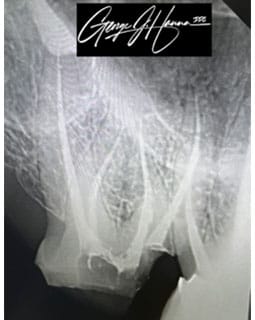

Endodontic treatments, sometimes referred to as root canals, are dental procedures used to clean out an infected root canal. Below the hard outer coating of your tooth lies a delicate tissue called “pulp.” The nerves and blood arteries in pulp provide your tooth with nutrition as it develops. When you reach maturity and your teeth are completely formed, the roots of your teeth can live without pulp and are no longer dependent upon it.

A root canal may be required to remove the pulp and any bacteria that remain when pulp becomes inflamed or infected. An untreated tooth abscess, which in turn may result in bone loss or complete tooth loss, may develop from an inflamed or infected pulp.

A root canal procedure involves numerous steps:

- To offer comfort and numb the injured region, the patient is given anesthesia

- To remove the affected tissue, a hole is cut in the tooth

- To get rid of microorganisms, the tooth canal is completely cleansed.

- To stop further infection, the canal is closed and sealed.

- To give the tooth a natural look, a crown may be applied. A tiny post may be placed into the root to support the crown in cases of severe root canal treatment.